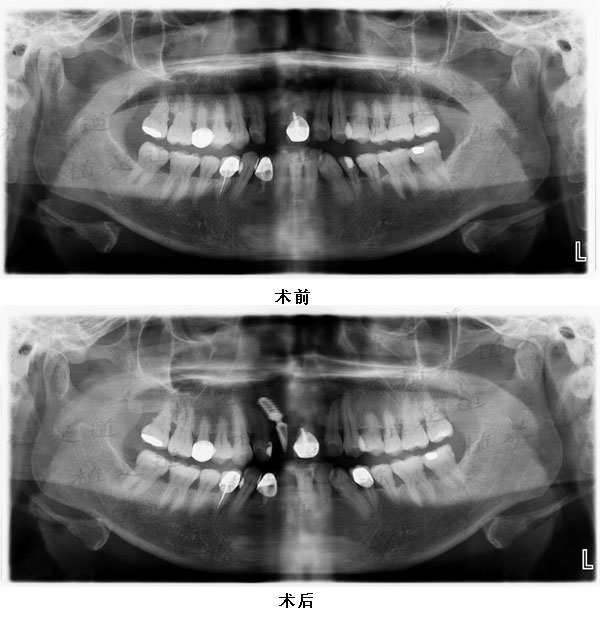

患者前牙HA涂层植体种植修复